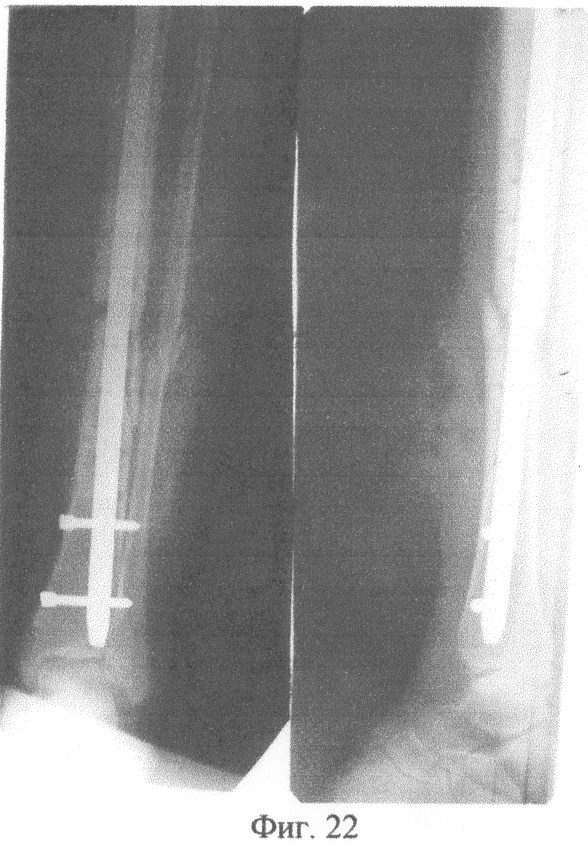

На фиг.1 изображено определение длины канюлированного стержня по отметке на шкале направляющей спицы. На фиг.2 – приведение в соответствие отверстий в блоке дистального целенаправителя отверстиям на рабочем конце канюлированного стержня с помощью контрольного инструмента. На фиг.3 – введение подготовленного канюлированного стержня по направляющей спице в костно-мозговой канал. На фиг.4 – выдвижение держателем направляющей спицы. На фиг.5 – контроль прохождения сверла через ниже расположенное отверстие на рабочем конце канюлированного стержня с помощью направляющей спицы и по отметке на шкале направляющей спицы. На фиг.6 – контроль прохождения блокирующего винта через ниже расположенное отверстие на рабочем конце канюлированного стержня с помощью направляющей спицы и по отметке на шкале направляющей спицы. На фиг.7 – контроль прохождения сверла через выше расположенное отверстие на рабочем конце канюлированного стержня и по отметке на шкале направляющей спицы. На фиг.8 – контроль прохождения блокирующего винта через выше расположенное отверстие на рабочем конце канюлированного стержня с помощью направляющей спицы и по отметке на шкале направляющей спицы. На фиг.9 – прохождение сверла впереди канюлированного стержня и проведение контроля отсутствия сверла в ниже расположенном отверстии на рабочем конце канюлированного стержня с помощью направляющей спицы и по отметке на шкале направляющей спицы. На фиг.10 – прохождение сверла позади канюлированного стержня и проведение контроля отсутствия сверла в ниже расположенном отверстии на рабочем конце канюлированного стержня с помощью направляющей спицы и по отметке на шкале направляющей спицы. На фиг.11 – сопротивление сверлу канюлированным стержнем и проведение контроля отсутствия сверла в ниже расположенном отверстии на рабочем конце канюлированного стержня с помощью направляющей спицы и по отметке на шкале направляющей спицы. На фиг.12 – определение спицей Киршнера ниже расположенного отверстия на рабочем конце канюлированного стержня и проведение контроля положения спицы Киршнера в ниже расположенном отверстии на рабочем конце канюлированного стержня с помощью направляющей спицы и по отметке на шкале направляющей спицы. На фиг.13 – контроль прохождения сверла через ниже расположенное отверстие на рабочем конце канюлированного стержня с помощью направляющей спицы и по отметке на шкале направляющей спицы. На фиг.14 – контроль прохождения блокирующего винта через ниже расположенное отверстие на рабочем конце канюлированного стержня с помощью направляющей спицы и по отметке на шкале направляющей спицы. На фиг.15 – сопротивление сверлу канюлированным стержнем и проведение контроля отсутствия сверла в выше расположенном отверстии на рабочем конце канюлированного стержня с помощью направляющей спицы и по отметке на шкале направляющей спицы. На фиг.16 – определение спицей Киршнера выше расположенного отверстия на рабочем конце канюлированного стержня и проведение контроля положения спицы Киршнера в выше расположенном отверстии на рабочем конце канюлированного стержня с помощью направляющей спицы и по отметке на шкале направляющей спицы. На фиг.17 – контроль прохождения сверла через выше расположенное отверстие на рабочем конце канюлированного стержня с помощью направляющей спицы и по отметке на шкале направляющей спицы. На фиг.18 – контроль прохождения блокирующего винта через выше расположенное отверстие на рабочем конце канюлированного стержня с помощью направляющей спицы и по отметке на шкале направляющей спицы. На фиг.19 – рентгенограмма левой бедренной кости в двух проекциях больного Квашнина Д.В. до операции. На фиг.20 – рентгенограмма левой бедренной кости в двух проекциях больного Квашнина Д.В. после операции. На фиг.21 – рентгенограмма костей левой голени в двух проекциях больной Корхалевой Е.Н. до операции. На фиг.22 – рентгенограмма костей левой голени в двух проекциях больной Корхалевой Е.Н. после операции.

Пример 2. Больная Корхалева Е.Н., 19 лет, медицинская карта 21093, госпитализированная в ортопедотравматологическое отделение Городской клинической больницы №21 города Уфы с диагнозом: закрытый оскольчатый несросшийся перелом средней трети обеих костей левой голени со смещением отломков с наличием металлоконструкции.

Одиннадцать месяцев назад после травмы произведена операция: открытая репозиция, накостный остеосинтез пластиной отломков большеберцовой кости левой голени, сращения перелома не наступило.

Сделана рентгенограмма левой голени в двух проекциях до операции (фиг.21). После обследования и предоперационной подготовки произведены операции.

Через верхнее отверстие в блоке дистального целенаправителя введен в сформированный канал блокирующий винт. Контроль прохождения блокирующего винта через выше расположенное отверстие на рабочем конце канюлированного стержня осуществлен следующим образом: держателем направляющая спица проведена в дистальном направлении по каналу стержня, она встретила сопротивление блокирующего винта на уровне выше расположенного отверстия на рабочем конце канюлированного стержня; по отметке на шкале направляющей спицы показатель равен 295 мм, что соответствует разнице между длиной канюлированного стержня (240 мм) и расстоянием от рабочего конца канюлированного стержня до уровня выше расположенного отверстия на рабочем конце канюлированного стержня (45 мм). Произведено проксимальное блокирование канюлированного стержня. Сделана контрольная рентгенограмма в двух проекциях передвижным рентгенаппаратом (фиг.22). Продолжительность операции 50 минут.